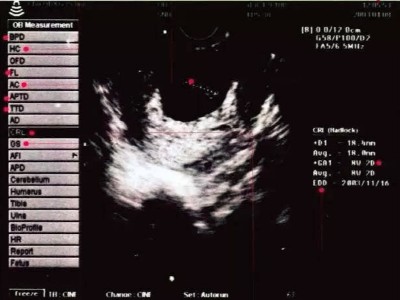

B超紙該如何看

當媽媽們拿到B超紙,B超紙該如何看呢-蘇州冠威

媽媽們在懷孕期間一般情況下需要做4-5次的彩超檢查,每一次的檢查對于媽媽們來說都尤為重要,那么,當媽媽們拿到B超紙時,看到上面的一些專業(yè)詞,B超紙該如何看呢?下面,小編就為大家來介紹一下。